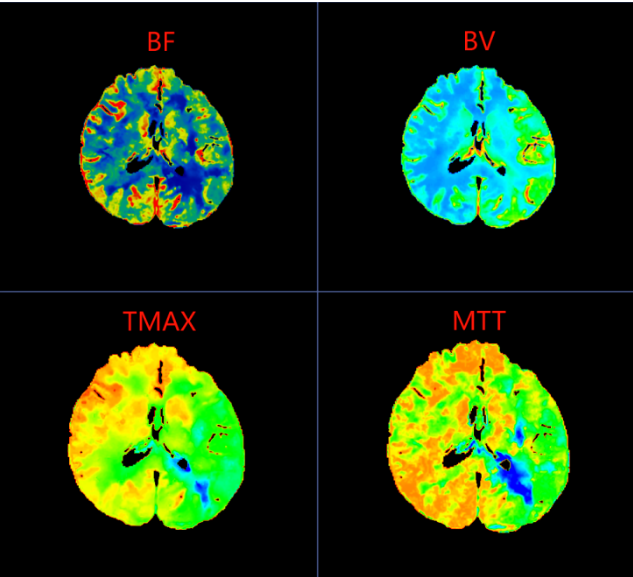

在脑梗死真正形成之前,大脑其实已经历一系列血流代偿与失代偿的过程。CTP(CT脑灌注成像)正是一种能够可视化脑血流动力学状态的前沿影像技术。它不仅能显示血管结构,更能精准评估脑组织的血流速度、血流量与血流通过时间,从而在患者尚未出现典型脑梗死症状时,就捕捉到脑灌注异常的“蛛丝马迹”。

李女士的CTP图像中,左侧大脑中动脉供血区呈现的“低灌注”表现,正是脑血流代偿机制开始崩溃的标志。这种梗死前的影像预警,为临床实施超早期干预——如强化抗血小板治疗、控制血压、改善脑灌注等——提供了至关重要的依据,从而有可能阻断病情进展,避免梗死发生。

2、CTP脑灌注成像:适用于疑似脑缺血前状态或短暂性脑缺血发作(TIA)患者,帮助评估脑血流储备与梗死风险。